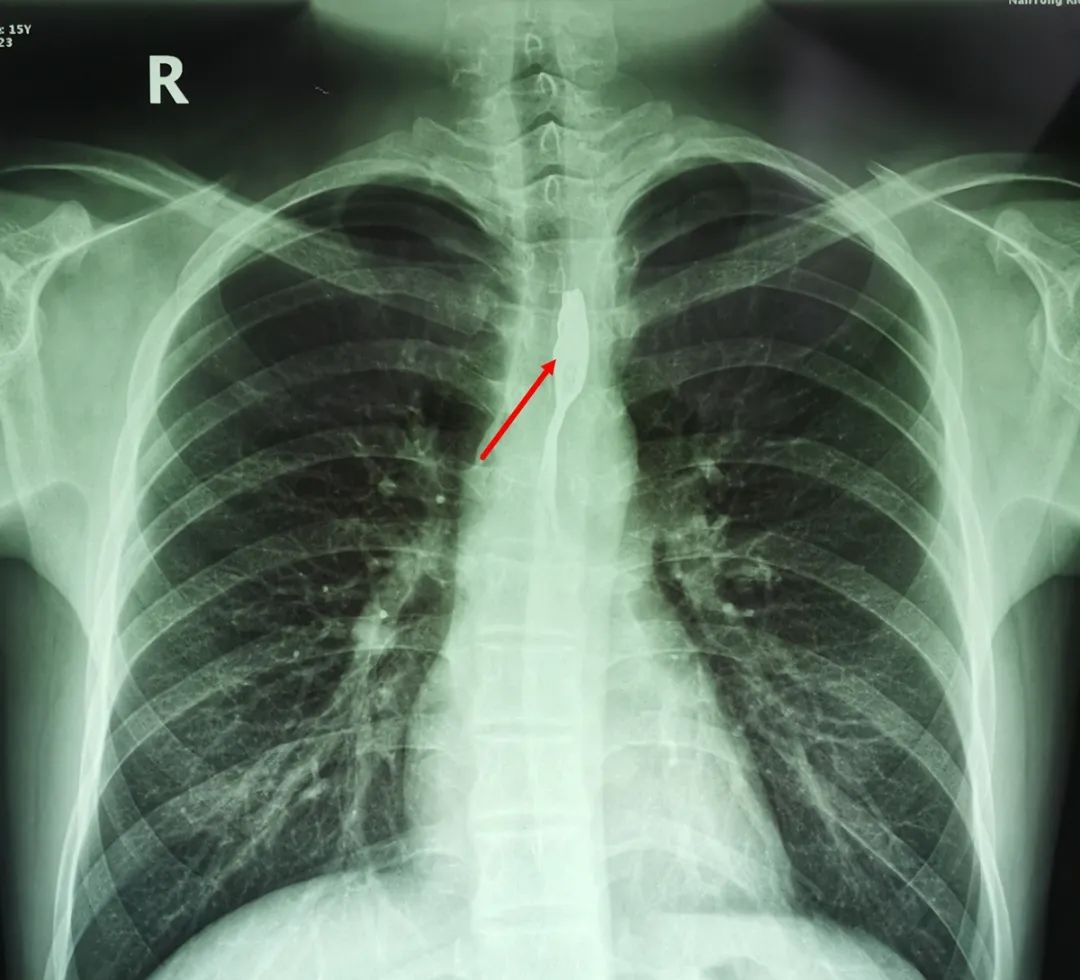

24日上午,啟東15歲男孩誠(chéng)誠(chéng)從南通瑞慈醫(yī)院康復(fù)出院了。上周五下午,誠(chéng)誠(chéng)在同學(xué)家玩耍,一邊說笑一邊吃鴨頭,竟然誤吞了一根鴨骨頭,頓時(shí)感覺一陣刺痛,家長(zhǎng)帶著他輾轉(zhuǎn)了兩家醫(yī)院也沒有解決問題,之后前往我院急診求助。

深夜11點(diǎn)半,我院耳鼻喉科副主任方崢嶸從家中趕到醫(yī)院,為誠(chéng)誠(chéng)進(jìn)行了急診手術(shù),從他的食管上段取出了一塊一端帶有尖刺,鋒利似刀片的鴨骨頭,化險(xiǎn)為夷。

據(jù)方崢嶸主任介紹,這根鴨骨頭有2.5厘米長(zhǎng),已經(jīng)劃傷了食管,取出時(shí)上面沾有血跡,所幸情況并不嚴(yán)重。他特別表揚(yáng)了誠(chéng)誠(chéng)和家長(zhǎng),在誠(chéng)誠(chéng)被鴨骨頭卡住后,他們沒有嘗試咽飯這一土方法,否則這塊銳利的鴨骨頭很有可能會(huì)刺破食管。他說,食管位于后縱隔,鄰近主動(dòng)脈、氣管、心臟等多個(gè)重要的組織結(jié)構(gòu),如若食管異物處理方式不當(dāng),損傷到的可能就不僅僅是食管,例如較大的魚刺如果強(qiáng)行吞咽就可能劃破主動(dòng)脈,造成大出血,危及患者性命。

△圖為:我院所取食管異物部分實(shí)例